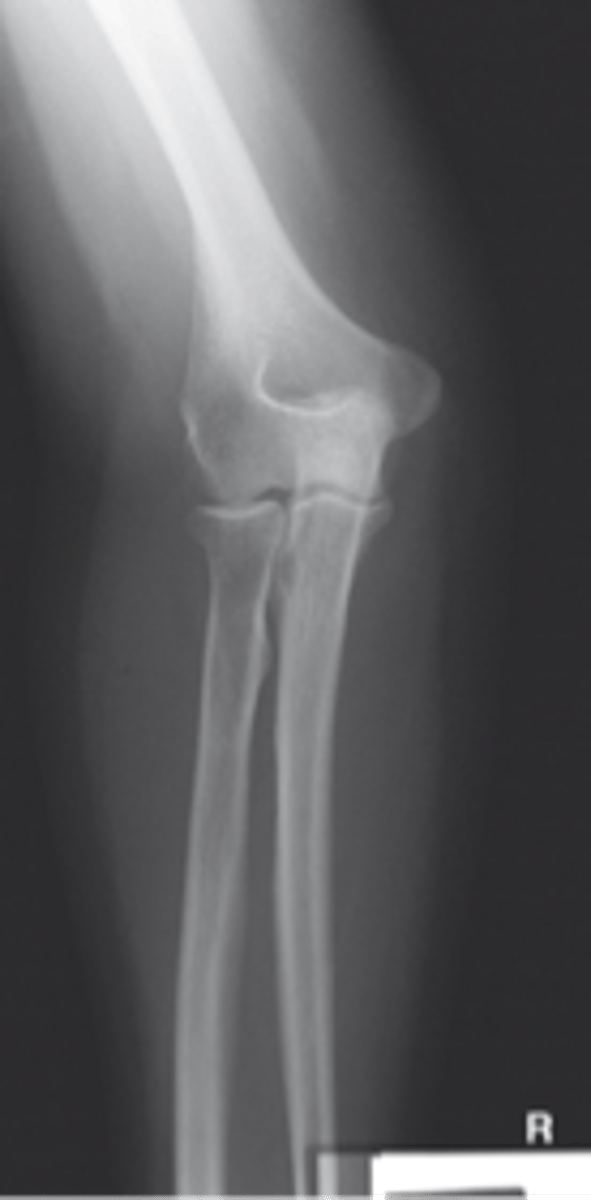

Lateral Elbow

Axial lateromedial for coronoid process elbow

Axial lateromedial for radial head elbow